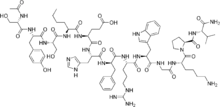

Afamelanotide has the amino acid sequence; Ac-Ser-Tyr-Ser-Nle-Glu-His-D-Phe-Arg-Trp-Gly-Lys-Pro-Val-NH2.

It is also known as [Nle4,D-Phe7]-α-MSH, which is abbreviated to NDP-MSH or NDP-α-MSH.